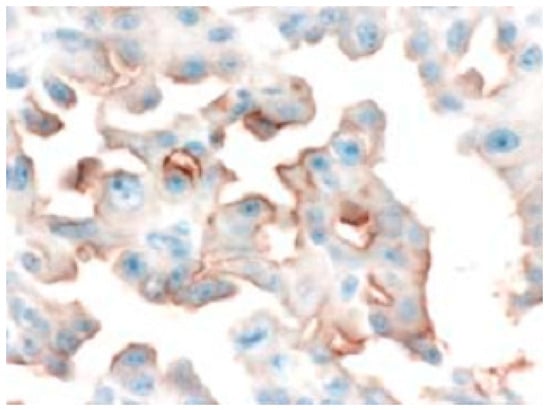

3.1. Immuhohistological Expressions of PEPT1 and ABCG2 Protein

- Yonemura, Y.; Endo, Y.; Canbay, E.; Liu, Y.; Ishibashi, H.; Takeshita, K.; Mizumoto, A.; Hirano, M.; Takao, N.; Ichinose, M.; et al. Selection of patients by membrane transporter expressions for aminolevulinic acid (ALA)-guided photodynamic detection of peritoneal metastases. Int. J. Sci. 2015, 4, 66–77. [Google Scholar] [CrossRef]

- Hagiya, Y.; Fukuhara, H.; Matsumoto, K.; Endo, Y.; Nakajima, M.; Tanaka, T.; Okura, I.; Kurabayashi, A.; Furihata, M.; Inoue, K.; et al. Expression levels of PEPT1 and ABCG2 play key roles in 5-aminolevulinic acid (ALA)-induced tumor-specific protoporphyrin IX (PpIX) accumulation in bladder cancer. Photodiag. Photodyn. Ther. 2013, 10, 288–295. [Google Scholar] [CrossRef]

- Hagiya, Y.; Endo, Y.; Yonemura, Y.; Takahashi, K.; Ishizuka, M.; Abe, F.; Tanaka, T.; Okura, I.; Nakajima, M.; Ishikawa, T.; et al. Pivotal roles of peptide transporter PEPT1 and ATP-binding cassette (ABC) transporter ABCG2 in 5-aminolevulinic acid (ALA)-based photocytotoxicity of gastric cancer cellsin vitro. Photodiag. Photodyn. Ther. 2012, 9, 204–214. [Google Scholar] [CrossRef] [PubMed]